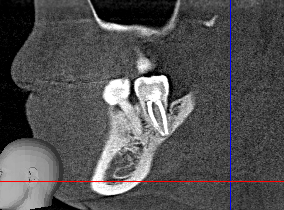

>Киста внутри зуба, в канале?

нет, киста за пределами зуба на конце корня. Происходит из-за того что в канале инфекция, она выходит за пределы зуба в кость образуя очаг воспаления, который организм изолирует фиброзной тканью.

>Как обнаружили кисту эту?

Сделать рентген или КТ.